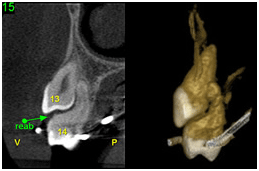

• Avaliar o grau de reabsorção radicular de dentes adjacentes a caninos retidos

Reabsorção radicular adjacente a dentes retidos Reabsorção radicular adjacente a dentes retidos